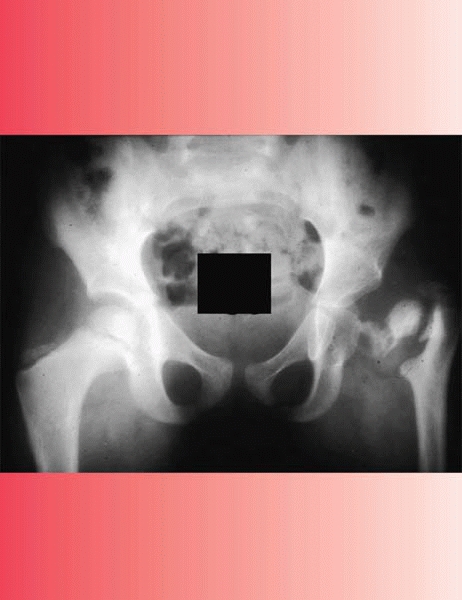

Beware when the CRP does not rapidly normalize in the first week after

surgery! You must ask yourself whether there is another collection of

fluid, whether the fluid reaccumulated, or if you have the right

diagnosis. Is it possible that you may have missed osteomyelitis of the

femoral neck? (See Fig. 16-5.) In this clinical scenario, it is best to get an MRI to determine why the child has not

![]() |

|

▪ FIGURE 16-5 An associated femoral neck osteomyelitis, as shown in this AP hip radiograph (arrow), delays improvement after an irrigation and debridement of the hip.